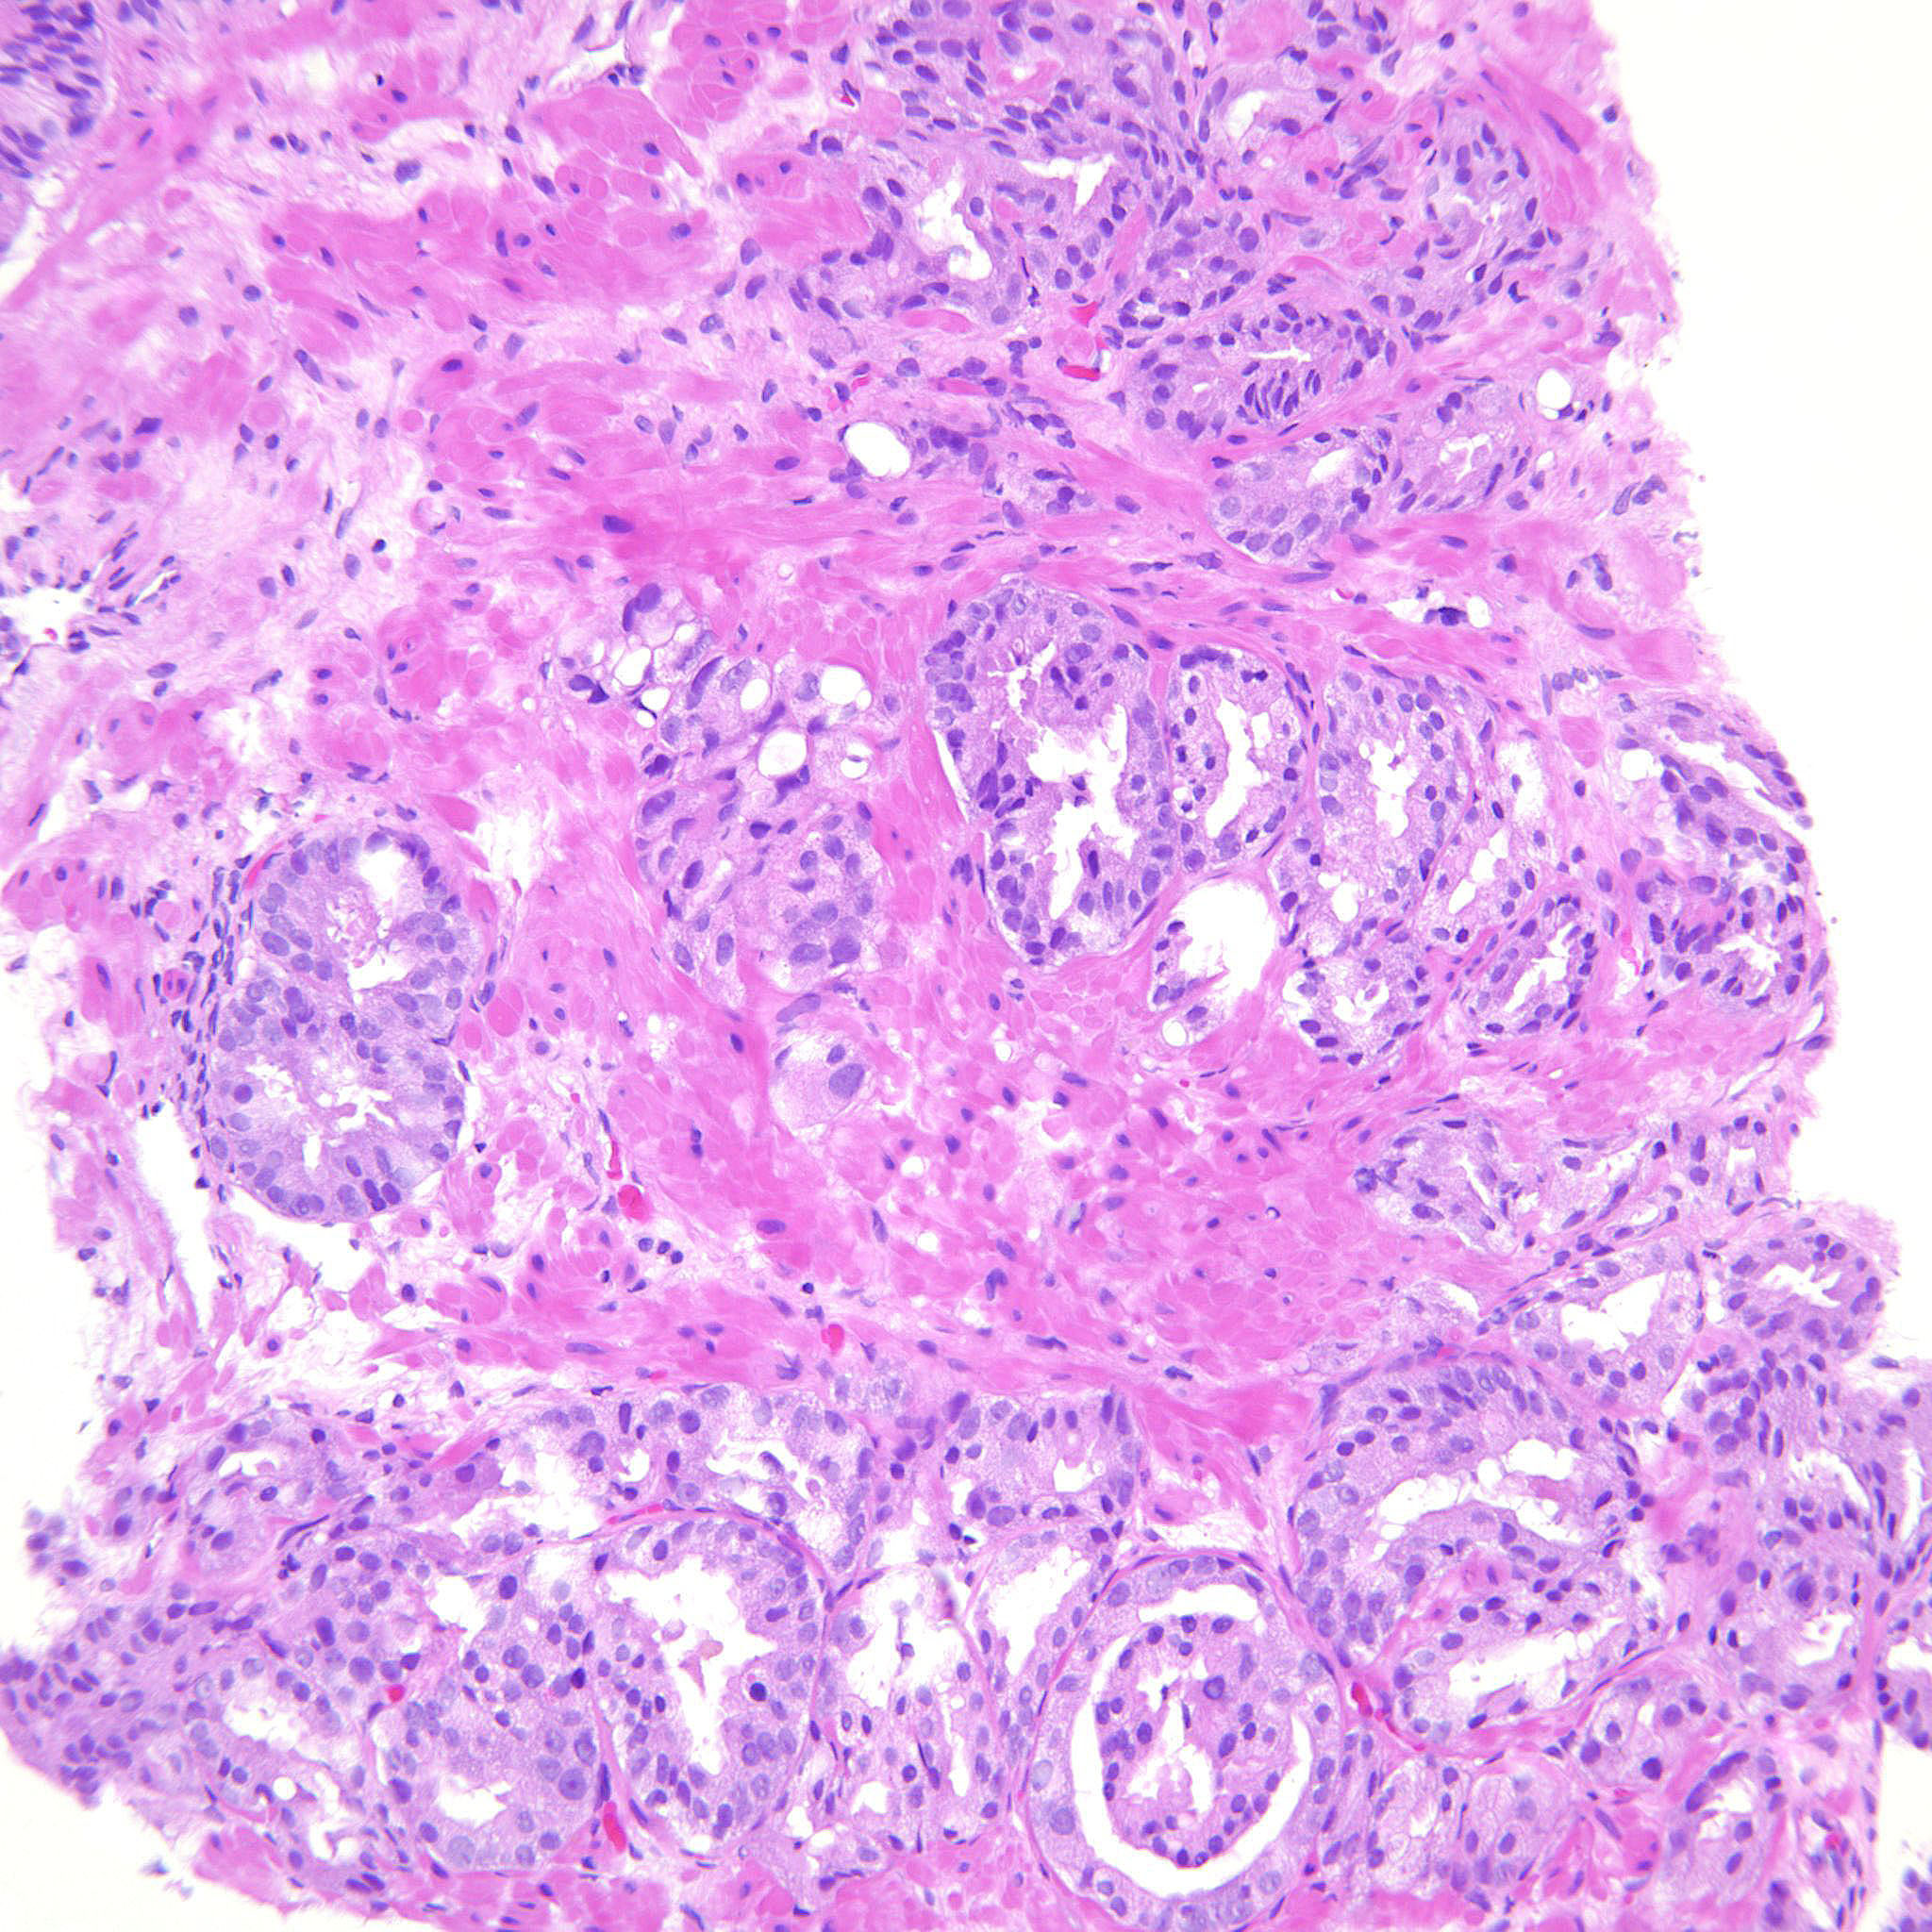

Case description (by case creator):

Gleason pattern 4 with glomeruloid bodies. There is also a GP 3 component.